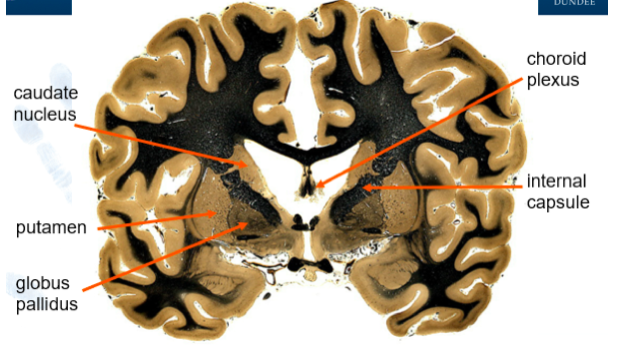

What does the caudate nucleus wrap around?

thalamus

What makes up the lentiform nucleus?

putamen

globus pallidus

What makes up the corpus striatum?

caudate nucelus and lentiform nucleus

What seperates the lentiform nucleus from the caudate nucleus?

internal capsule